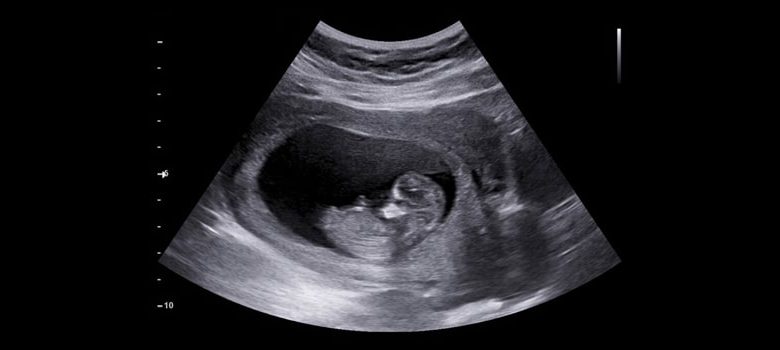

ما هي مراحل تكوين الجنين؟ ومن أي يوم تبدأ أعراض الحمل؟

- تبدأ الأوعية الدموية الموجودة داخل بطانة الرحم الصغير وذلك تحت تأثير هرمونات مثل الاستروجين والبروجسترون وعند اليوم الرابع عشر يصبح هذا الجنين الصغير جزء لا يتجزأ من الرحم، وتبدأ منطقة الغرس بالشفاء ويحصل في بعض الأحيان نزيف بسيط وقد يخطأ كثير من النساء وتتعبر هذا الدم هو بسبب بدء الدورة الشهرية ولكنه يكون بسبب حدوث الحمل الذي يكتشف بعد ذلك.

- تنمو المشيمة وتتصل بالجنين بساق الاتصال بالجنين ويسمى بالحبل السري وتحتوي المشيمة على نفس جينات الجنين لذلك يمكن أخذ عينات منها لإجراء ببعض الفحوصات الخاصة بجينات محددة أو أي مشكلات خاصة بالصبغات.